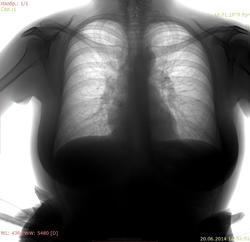

Пациентка 1979 г.р., жалоб активно не предъявляла. Есть ли признаки нарушения бронхиальной проходимости (гиперпневматизация верхушек, уплощение диафрагмы)?

Есть ли признаки нарушения бронхиальной проходимости (гиперпневматизация верхушек, уплощение диафрагмы)?

Уплощение диафрагмы можно лишь на скопии или на вдохе-выдохе, двумя снимками поймать. Гиперпневматизацию оценить сейчас проблематично. Цифра играет совсем не режимно, и это бывает критично. А ещё бывает форма грудной клетки такая, конституциональная.)) Поэтому архив хорошо, а насмотренность вариативности нормы - лучше!)

Я бы норму писала.

Норма, просто не глубоко вдохнула, по сравнению с архивом.

Норма.